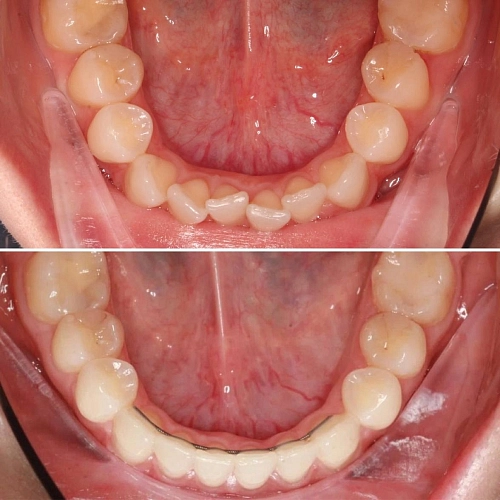

Лечение выраженной скученности без удаления зубов с применением элайнеров

Скученность зубов — это распространенная проблема, с которой сталкиваются многие люди. Она может вызывать не только эстетические неудобства, но и проблемы с жеванием и гигиеной полости рта.

Лечение скученности зубов с помощью элайнеров — это современный и эффективный способ достичь желаемой улыбки без необходимости удаления зубов.